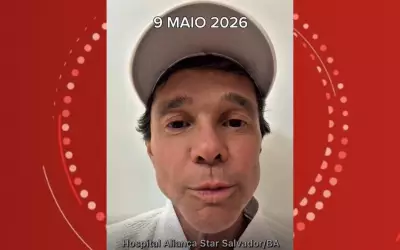

Netinho anuncia volta do linfoma e passará por biópsia

O cantor Netinho revelou que o linfoma voltou, após quase um ano em remissão. Ele fará biópsia para definir o tratamento e afirma que enfrentará a doença com positividade.